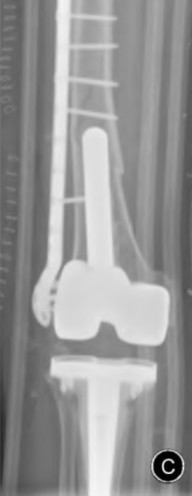

During a revision total knee arthroplasty, removal of the tibial component reveals a massive contained metaphyseal defect measuring 3 cm deep, but with an intact cortical rim. According to the Anderson Orthopaedic Research Institute (AORI) classification, what type of defect is this, and what is the preferred method of management?

Explanation